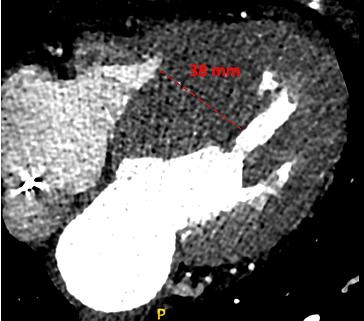

The procedure was performed under conscious sedation and local anesthesia. As mentioned in our previous study,11 femoral artery access was achieved using two 6-French sheaths—one for the guiding catheter to deliver the ablative agent and another for continuous monitoring of the midventricular gradient throughout the procedure. Femoral venous access was also obtained to place a temporary pacemaker in the right ventricular apex, ensuring readiness to manage potential advanced atrioventricular (AV) blocks during the procedure. A pigtail catheter was positioned in the left ventricle to establish baseline midventricular pressure gradients. Following this, the Brockenbrough-Braunwald-Morrow sign was evaluated, characterized by a post-extrasystolic increase in gradient, confirming dynamic obstruction at the midventricular level13 (Figure 4A).

Coronary angiography was performed to identify an appropriate septal branch supplying the midventricular myocardium, typically visualized in right anterior oblique projections (Figure 5A). A 0.014-inch guidewire was advanced into the chosen septal artery, and an over-the-wire balloon catheter was positioned to ensure vessel occlusion without contrast leakage. A contrast agent was initially injected selectively under fluoroscopy to confirm the target vessel, observe the absence of contrast leakage, and verify its supply to the hypertrophied myocardium. Once the target vessel was confirmed, polidocanol was injected into the balloon-occluded artery to achieve controlled ablation (Figure 5B). The final angiographic image confirmed the successful occlusion of the septal artery while preserving normal blood flow in the left anterior descending artery (Figure 5C). TTE revealed septal brightening at the target site during this process, confirming accurate delivery to the intended region (Figure 6). Polidocanol was infused through the balloon catheter in incremental doses, with its foam-like structure enabling focused ablation across the hypertrophied midventricular myocardium. Doses ranged from 2 to 7 mL depending on vessel size, hemodynamic responses, and real-time electrocardiographic changes, such as QRS widening. The procedure was deemed successful if a reduction of 50% or more in the midventricular pressure gradient was achieved immediately post-ablation, as verified by hemodynamic and echocardiographic measurements. Additionally, the resolution of the Brockenbrough-Braunwald-Morrow sign (Figure 4B), which served as an important marker to guide the effectiveness of the ablation procedure, along with the absence of significant complications, such as high-degree AV block or sustained ventricular arrhythmias, were key indicators of procedural success and safety.